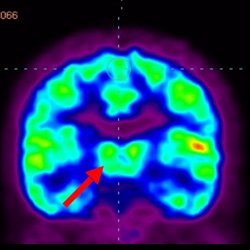

細胞治療后,藍色和黑色區域減少,并且看到更活躍的區域。這表明損傷減少并改善了大腦功能。

細胞治療前 PET CT 掃描顯示神經組織中的藍/黑色區域,表明腦癱引起的大腦損傷。

這證明細胞療法是治療腦癱兒童安全有效的方法。細胞療法可以更新大腦損傷的核心,并且可以通過 PET CT 掃描來監測大腦的改善情況。這些細胞療法與標準治療一起促進腦癱兒童的生長和改善。